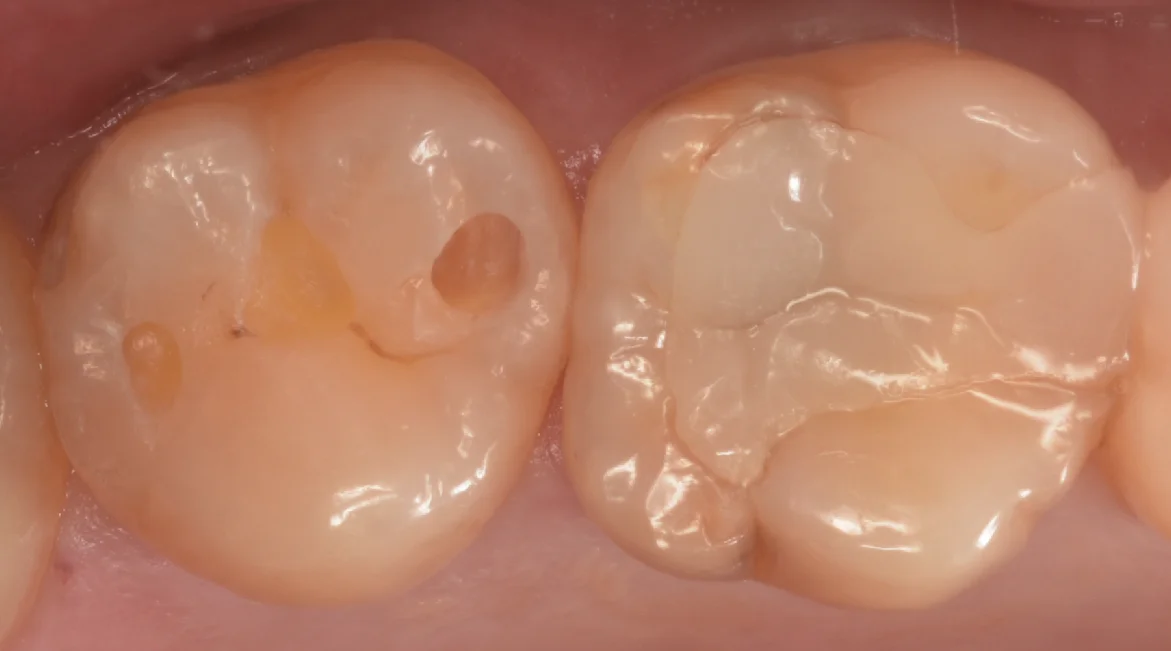

そして取り切ったのがこちらになります。

綺麗な歯の色が出たのがわかるかと思います。

状況としては個人的にはまだ1〜2年くらい様子見でも良かったような気もしますが、患者さんからの強い希望があったためこのまま介入することとなりました。

やるからにはきっちりやりたいので、なるべく歯の削除量を抑えた上でしっかりと虫歯を取り切りました。